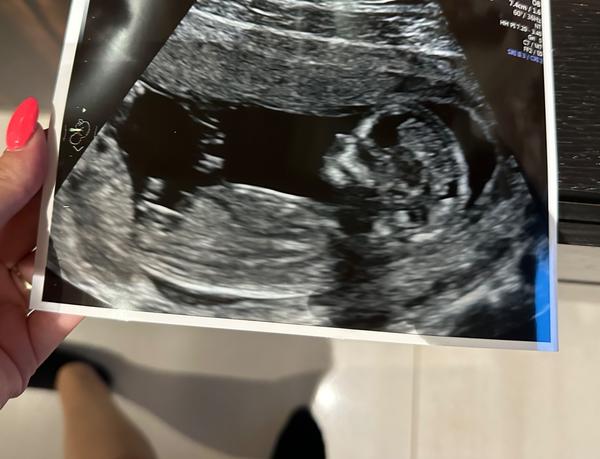

chtěla jsem se zeptat, zda je z fotky vidět pohlaví?

Myslela jsem, že to je nožička a ne pohlavní hrbolek, ale

nerozumím tomu🙂

z fotografie lze těžko říci, bylo by potřeba vidět "naživo". ☹